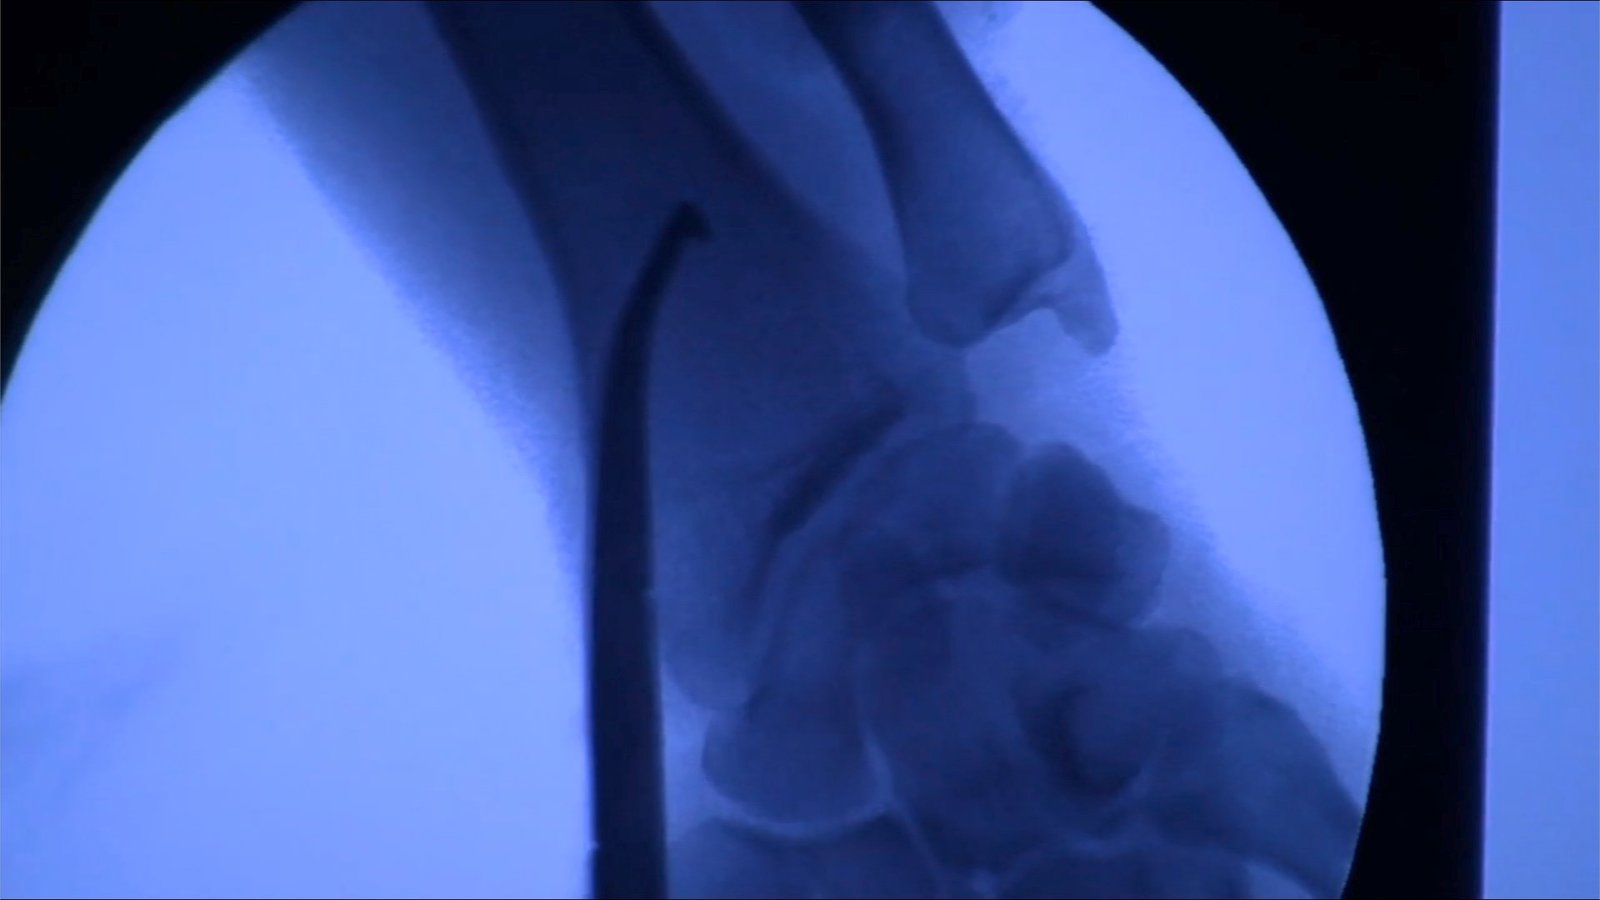

En el especial “LOS ABDUCIDOS”, que History estrena el próximo lunes 25 de abril, Maussan presenta tres supuestos casos de abducción. La primera historia es la de Ron Noel, un hombre de Florida posiblemente abducido de niño, que poseía un extraño implante dejado en su muñeca y que fue extraído quirúrgicamente ante la cámara. El instrumento foráneo transmitía señales hacia el espacio profundo. El segundo caso que presenta Maussan en este especial, que sucedió en los suburbios de Colorado, es el de Stan Romanek, quien asegura ser acosado por inteligencia militar y tiene evidencia y testigos de los fenómenos en torno a sus múltiples abducciones. Finalmente, LOS “ABDUCIDOS” cuenta la historia de Travis Walton, un leñador que relata cómo fue derribado por un haz de luz en las montañas de Arizona para reaparecer cinco días después. Su historia fue retrata en la película Hollywoodense de 1993 “Fire in the sky” (“Fuego en el cielo”).